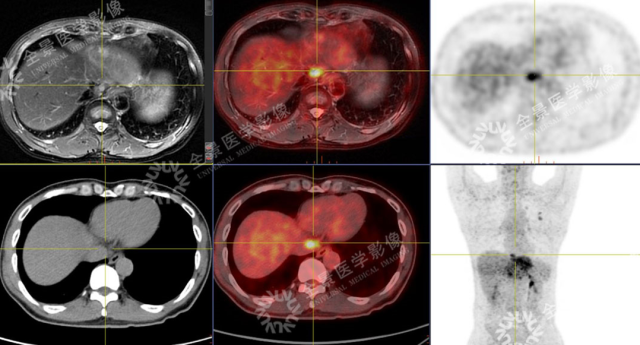

男性,57 岁,上腹疼痛 2 月余,加重 1 周。外院 CT:肝左叶占位。既往有乙肝病史多年。

SUVmax = 4.59

PET 示:腔静脉裂孔处结节 FDG 摄取增高;

CT 示:无明显异常密度影。

怀疑:腔静脉癌栓?后心膈角区淋巴结?

确诊:腔静脉癌栓